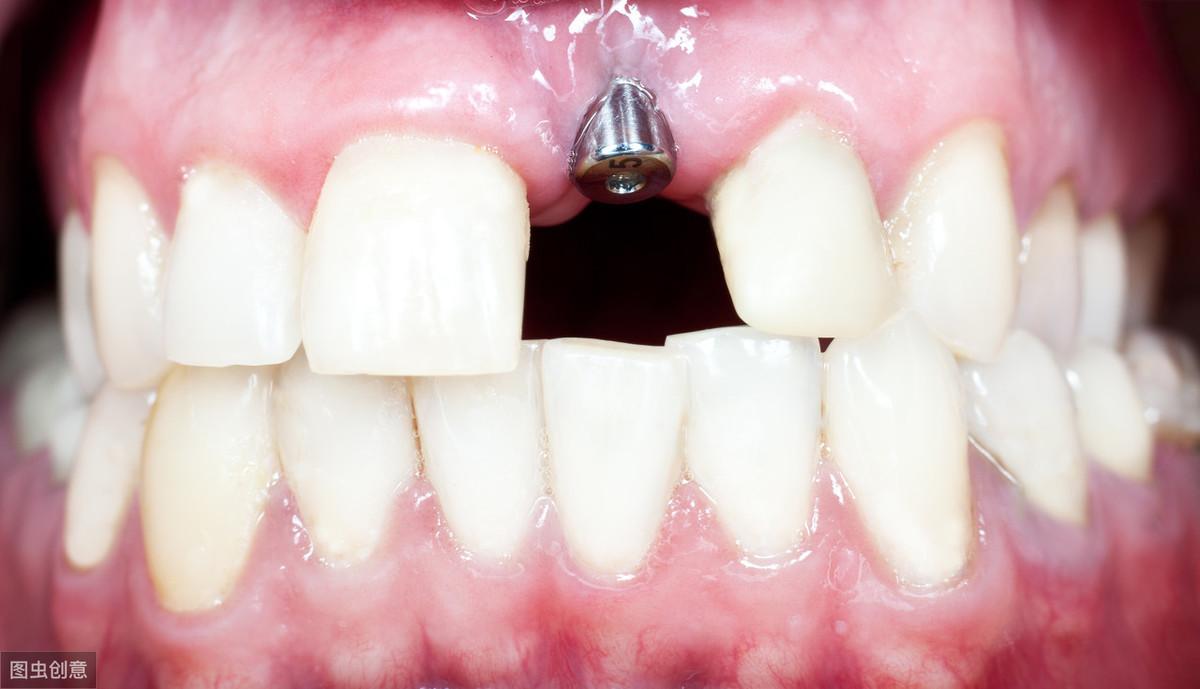

種植牙手術示意圖

種植牙技術是近幾十年出現(xiàn)在大眾視野中的一種修復缺失牙體的方法。一顆完整的種植牙體由三部分組成:種植體、基臺、人工牙冠。

手術過程就是將種植體植入患者的牙體缺失處,待其傷口愈合,種植體與牙槽骨結合牢固后,將基臺安裝在種植體上,再將人工牙冠安裝在基臺上,形成完整而堅固的人工牙體。

種植牙技術就像在缺失牙體處種一顆新的牙齒,能夠和牙槽骨結合,做種植牙能有預防牙槽骨萎縮,這是普通的假牙無法做到的,而且種植牙體不依附周圍鄰牙,對鄰牙不造成任何負擔,所以相對其他修復手段,不僅更為牢固不易松動,且使用壽命長,果好。